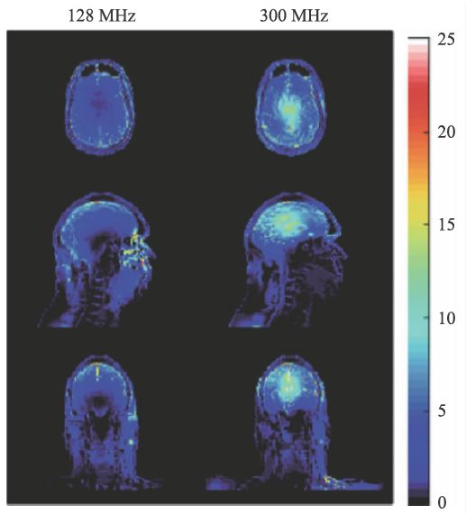

SAR值升高是射頻場另一個問題,隨著射頻頻率的提高,組織對射頻能量的吸收急劇上升,可導致組織局部的溫度升高。SAR值的計算可由式9表示。

σ為組織電導率,ρ為組織密度。對于SAR值各國和國際組織均有嚴格的限制,因為過量的射頻能量的吸收可能會對受試者造成危害。

圖14 是一個SAR值對大腦溫度升高的一個仿真結果[14],對于平均SAR=3 W/kg的頭部掃描,7 T(右側)下的溫度升高顯著高于3 T(左側)。因此在超高MRI中均需要配置一個可靠的SAR值監(jiān)控裝置。

圖14 局部SAR值的仿真結果